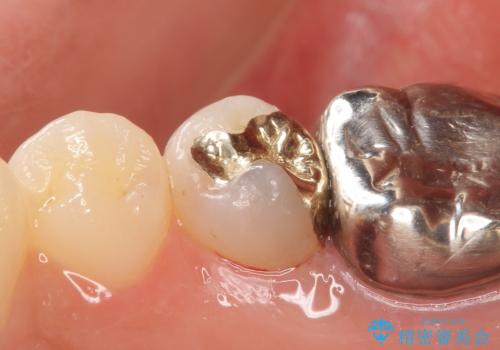

- 右下5番目の歯がしみるといらっしゃった方の症例です。

銀歯及び虫歯を除去し、適合に優れたPGA(ゴールド)インレーにて修復を行いました。

ゴールドは化学的な安定性が高いため変色や腐食がほとんどなく、アレルギーなども起こりにくい人体に優しい素材です。

また硬さも天然歯に近いため周囲の歯への影響も少なく、さらに適合もよいため虫歯の再発も少ない、とても補綴に適した材料です。